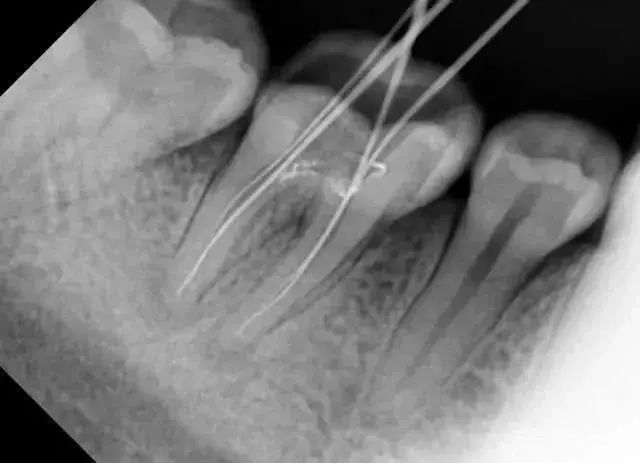

- 比如,当拔除下颌智齿时,仅凭口内检查无法发现它离神经管的位置

因此,如果牙齿出了问题,齿科医生就需要有“透视”功能的X线片来检查。通过x线片不仅能了解牙齿本身的病变情况,还可以了解牙根下有没有囊肿、周围骨头有没有吸收以及牙槽骨内是否有埋伏牙、多生牙等。依据X线片综合分析,可以提高齿科医生诊断治疗牙齿的准确性和成功率。

要了解个别牙根及周围变化,则选择拍摄小牙片。医生要判断牙槽骨是否符合种植条件,或者了解埋伏阻生齿的三维位置以及其他颌骨内病变组织的形态大小时,则需要进一步拍摄 CBCT 。